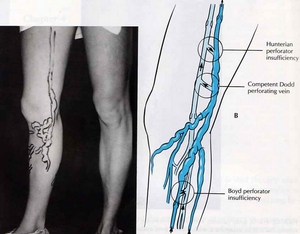

(4) SEPS (subfascial endoscopic perforator surgery)

利用北醫整形外科極為成熟的顯微手術與內視鏡技術, 將皮膚下已經喪失功能的穿透支血管夾住, 避免重新打通(recannalization)或心血管增生(neovascularization), 減少再發率(recurrence or retreatment rate).